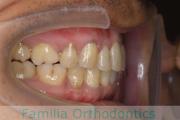

No.22V-409

- 叢生

- 16歳

- 女性

- 抜歯部位

- 上:

- 44

- 下:

- 8|58

- 主な使用装置:

- FEA

- 治療にかかった費用:

- 86万円

八重歯を治したいということで来院されました。下あごの左ずれのある上顎前突(出っ歯)・叢生(でこぼこ)でしたので、上は左右から、下はで左のみ小臼歯を抜歯して、歯科矯正用アンカースクリューとマルチブラケット法にて治療を行いました。2年強、30回程度の通院が必要でした。

上下とも前歯の叢生(でこぼこ、凹凸、ガタガタ)があるため、保定を怠ると後戻りのリスクがあります。